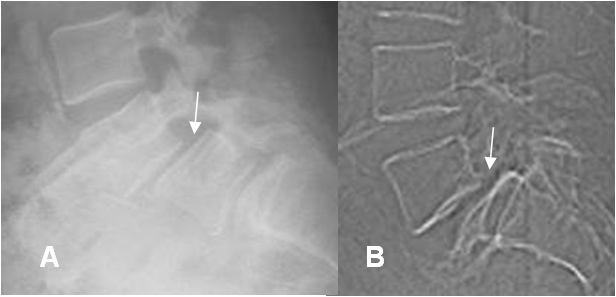

Fig 78. Anterolistesis G II.

A: Rx lateral, B: TAC reconstrucción sagital. Anterolistesis GII, con desplazamiento del cuerpo superior, entre el 25 y 50%. Adicionalmente en A, hay otra anterolistesis GI, en el segmento inferior.